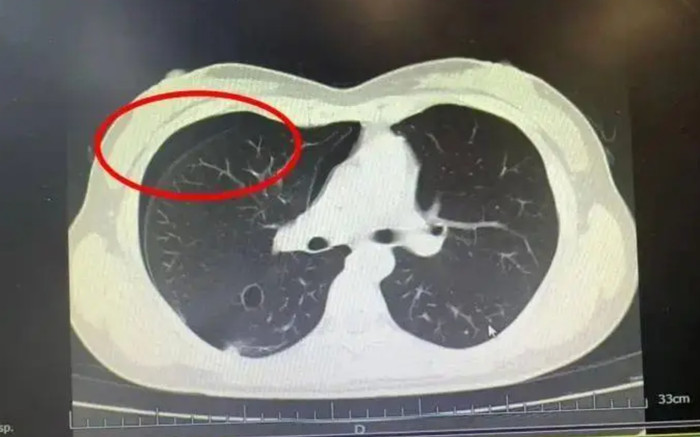

Ngay lập tức, cô được đưa đến khoa Hô hấp của Bệnh viện Nhân dân số 3, quận Dư Hàng. Bác sĩ Hà Lập Hàng, sau khi kiểm tra CT ngực, chỉ có thể lắc đầu và thông báo: "Phổi của cô bị ‘nổ’ rồi! Cô mắc chứng tràn khí màng phổi tự phát. Cần nhập viện ngay để thực hiện chọc hút khí và đặt ống dẫn lưu".

Kết quả chụp CT cho thấy người phụ nữ bị tràn khí màng phổi tự phát. (Ảnh: Sohu)